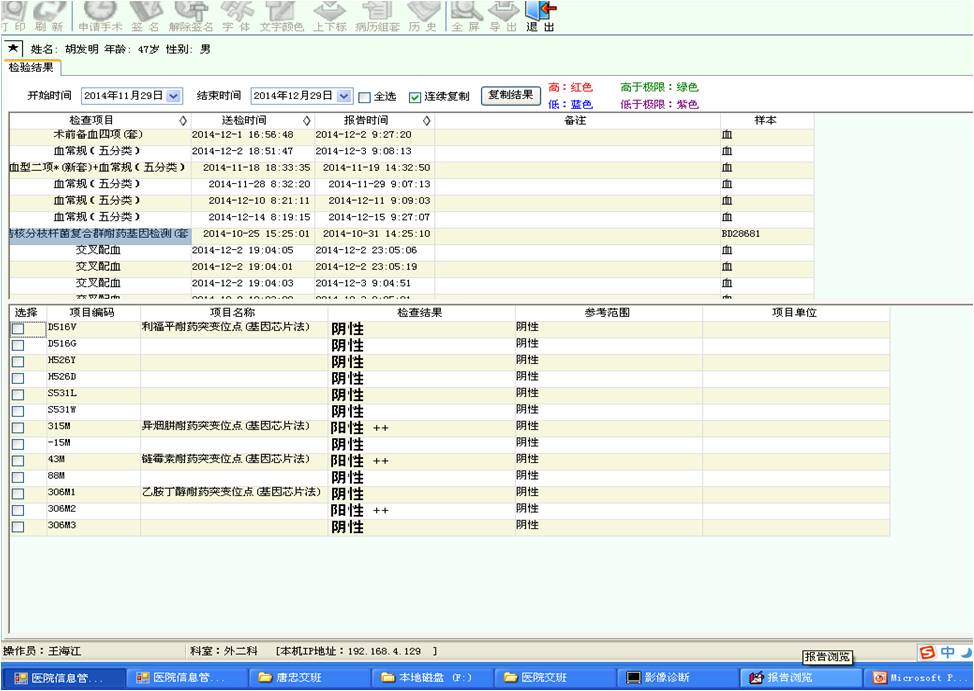

术前耐药检查阳性